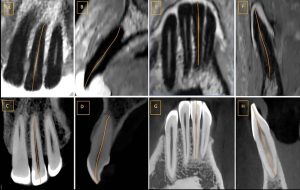

1. Periapical X-rays- Here, the X-ray image taken with the help of a sensor helps in viewing the crown up to the root region including the surrounding bone at the apex in the upper or the lower jaw whichever is targeted. These X-rays help in detecting endodontic and periodontal lesions, tooth decay, bone loss, etc.